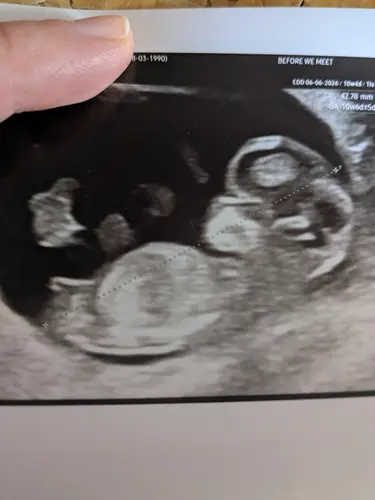

Hay! Dit is de 12 weken echo

Hoi allemaal! Is dit dan een meisje? Omdat het redelijk recht lijkt?